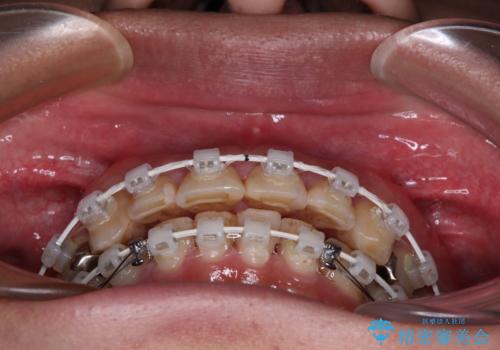

銀歯を白くしたい 一緒に矯正治療も行ない美しい口腔内に

抜歯が必要な歯は事前に抜歯をし、その後ワイヤー装置にて歯列矯正を行い、途中でインプラントを埋入し、オールセラミッククラウンにて補綴治療を行うこととしました。

矯正治療にやや時間がかかりましたが、歯列はきれいに整い、気になっていたむし歯や銀歯は自然な色合いに仕上がりました。